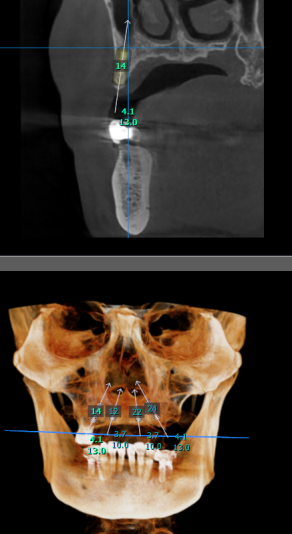

Good day to everyone, recently a gentleman came to my practice, requesting for implants to replace his upper non retentive complete denture. After taking the CBCT, i noticed that the remaining alveolar bone width and height are just sufficient for the all on 4 concept based on literature (5mm width and 10mm height). My surgical plan is as follows

2. Ridge expansion at planned implant site with densah bur and placement of 2 units 3.7x10mm at the anterior and another 2 units of 4.1x13mm implant at the posterior region followed by bone grafting with Ethoss. Temporisation with printed resin prosthesis.